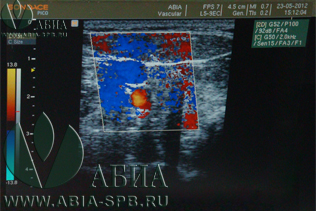

Наиболее информативное на данный момент исследование сосудов - Дуплекс / триплекс сосудов. Триплекс сосудов - это дуплексное сканирование с цветным картированием. Триплексное сканирование сосудов - это единственное на данный момент ультразвуковое исследование, которое показывает направление кровотока и степень влияния на кровоток имеющихся стенозов, тромбов и бляшек.